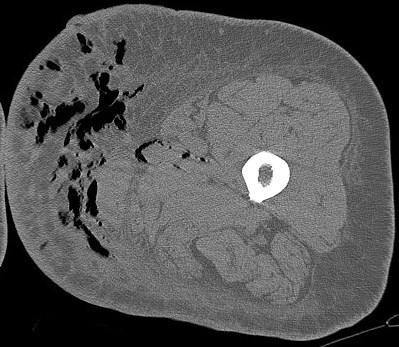

Figure 4 for case Necrotizing fasciitis ( RID3447 )

Figure 4

The soft tissue air is essentially pathognomic. Reference article.

Necrotizing fasciitis ( RID3447 )